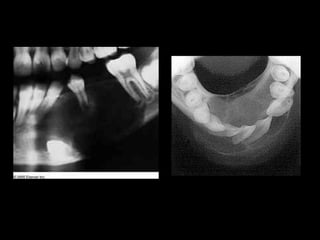

1.COMPLEX: most common in posterior mouth.

Amorphous conglomeration of dental tissues

consisting of enamel,dentin and cementum. Radiograph

shows gives a radiopaque mutilobular appearance.

2.COMPOUND: common in anterior jaw.contains

numerous denticles or tooth like fragments (each

containing enamel with dentin and pulp)

3. Radiographical resembles a bag of teeth